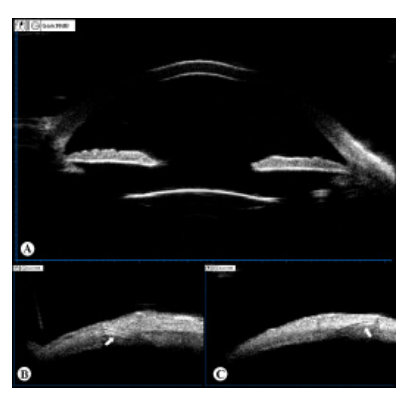

患者,男性,73岁,“左眼因外伤行晶状体摘除术后4月余”于2019年07月22日就诊,拟行二期IOL植入术。入院前4月余,患者因左眼钝伤导致“左眼晶状体半脱位、左眼视网膜脱离”在我院行“左眼玻璃体切除+脱位晶状体切除+视网膜脱离修复术”,术后视网膜伏贴良好。无特殊既往病史。入院诊断为:1)左眼无晶体眼;2)左眼视网膜脱离修复术后。入院检查:VOD 1.0,VOS 0.02,矫正视力1.0(+9.50DS/−1.25DC×90°),双眼眼压正常。右眼未见异常;左眼角膜透明,瞳孔圆,直径约4 mm,虹膜震颤,晶状体缺如;散瞳检查:无晶状体囊膜残留,视网膜贴伏。左眼眼轴长度23.56 mm,角膜内皮细胞密度为1684.3 /mm2。顺利行“左眼改良YAMANE式后房型IOL巩膜固定术”[Sensar AR40(Johnson & Johnson),22.0D, SRK/T公式,预留目标屈光度− 0.33D]。术后第一天,裸眼视力0.7,眼压11.9 mmHg(1mmHg=0.133 kPa),IOL位正。术后5个月,裸眼视力0.8,矫正视力0.9(+0.50 DS/ − 1.50DC×90°),眼压13.3 mmHg,角膜内皮细胞密度 1644.4 /mm2;IOL位正(图1A),其襻在巩膜层间固定良好(图1B~C)。随访期间视力稳定,无IOL移位、偏心、脱位及襻暴露等并发症。

图 1 改良 YAMANE 式后房型 IOL 植入术后

Figure 1 The position of IOL following the scleral fixation of posterior chamber intraocular lens using the modified YAMANE’s technique

(A) 超声生物显微镜检查 IOL 在眼内位正,无明显倾斜;(B~C) IOL 襻 ( 白色箭头 ) 在巩膜隧道内固定。

(A) Under ultrasound biomicroscopy, the IOL showed well centered without obvious tilt. (B&C) The IOL haptics (white arrow) were fixed in the scleral tunnel.